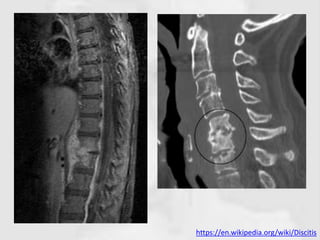

DISCITIS

INTRODUCTION

• Infection limited to the intervertebral disc is

rare

• Usually due to direct inoculation

– Following discography

– Chemo-nucleolysis

– Discectomy

• The vertebral end-plates are rapidly attacked

and the infection then spreads into the

vertebral body

https://en.wikipedia.org/wiki/Discitis

RADIOGRAPHIC FEATURES

PLAIN RADIOGRAPH CT

• Insensitive to the early changes of

diskitis/osteomyelitis,

• Normal appearances being maintained

for up to 2-4 weeks.

• CT findings are similar to plain film

• More sensitive to earlier changes.

• Thereafter disc space narrowing and

irregularity or ill definition of the

vertebral endplates can be seen.

• Additionally, surrounding soft tissue

swelling, intervertebral disc

enhancement with contrast, collections

• In untreated cases, bony sclerosis may

begin to appear in 10-12 weeks.